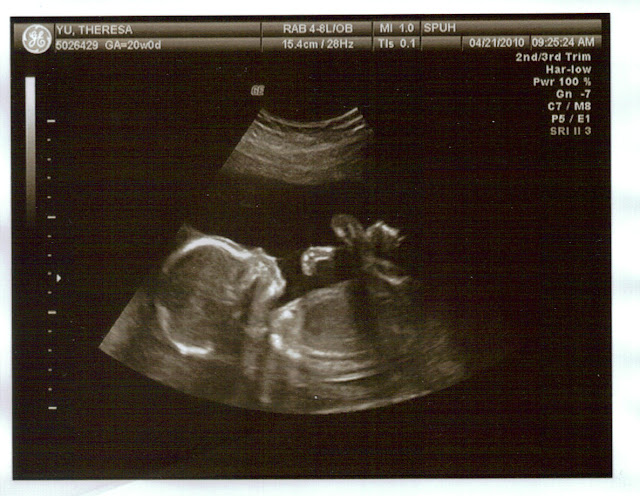

The baby seems to be just chilling out - feet up, not a care in the world.

This is the shot where they determined the sex of the baby. I love that they added the little pointer in the picture - hello! Who says you have to be out of the womb before parents can share embarrasing photos of you?